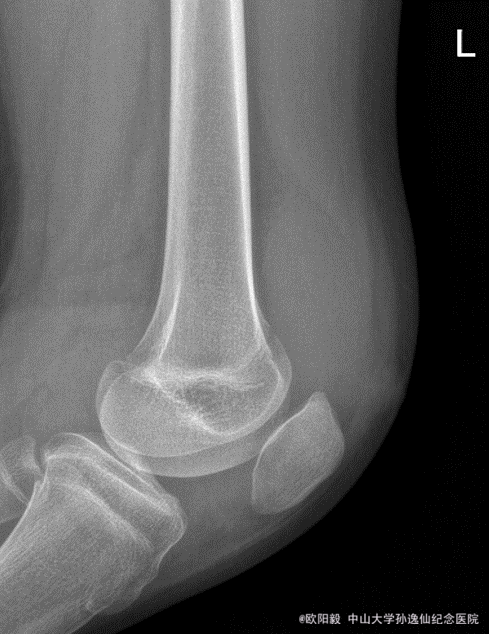

患者女,10岁,因“摔伤致左膝关节反复肿胀1年余”入院。患者1年前摔伤后出现左膝关节肿胀,无明显发热,6个月前曾在外院开放下行左膝滑膜病灶清理术,症状有缓解,但症状仍然反复,余未见明显异常。

查体:左膝关节浮髌征(+),血沉 80,C反应蛋白 15.2,关节液白细胞 41253,余未见明显异常。X线未见明显异常,MRI检查可见髌上囊大量积液。

诊断:左膝关节肿胀查因:感染?拟行左膝关节镜检,病灶清理术。